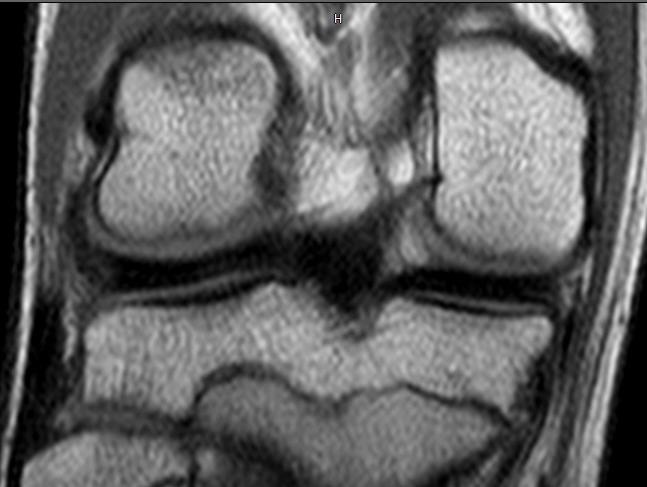

Միայն Վնասվածքաբանության և օրթոպեդիայի գիտական կենտրոնի Մանկական վնասվածքաբանության և օրթոպեդիայի բաժանմունքում կատարված հետազոտության ընթացքում ի վերջո կլինիկորեն ախտորոշվել է միջային մահիկի վնասումը, որը հաստատվել է նաև մագինսառեսոնանսային հետազոտության ընթացքում:

ԱՐԴՅՈՒՆՔ . Կատարված արթրոսկոպիկ վիրահատությունը հիվանդին թույլ կտա ՇԱՐՈՒՆԱԿԵԼ ԶԲԱՂՎԵԼ պրոֆեսիոնալ ֆուտբոլով, քանի որ վնասվածքը հայտնաբերված է ժամանակին, բուժված է ադեկվատ կերպով և հետևաբար կարճ ժամանակում ծնկան հոդի ֆունկցիան լիովին կվերականգնվի:

. Ի տարբերություն մեծահասակների, երեխայի մոտ ժամանակին կատարված ախտորոշման և վիրահատական միջամտության շնորհիվ կարելի է ոչ թե հեռացնել, այլ վերականգնել վնասված հյուսվածքը, ոը թույլ կտա ամբողջովին վերականգնել հյուսվածքի ֆունկցիան: Ու մեր կլինիկայում այսօր մենք այդ միջամտությունները կատարում ենք նվազ ինվազիվ ու շատ արդյունավետ արթրոսկոպիկ եղանակով: